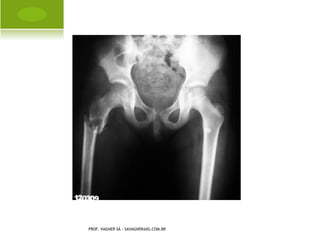

T RANSTROCANTÉRICA    E

ACETÁBULO

PROF. VAGNER SÁ - SAVAGNER@IG.COM.BR

SUBTROCANTÉRICA

DIÁFISE